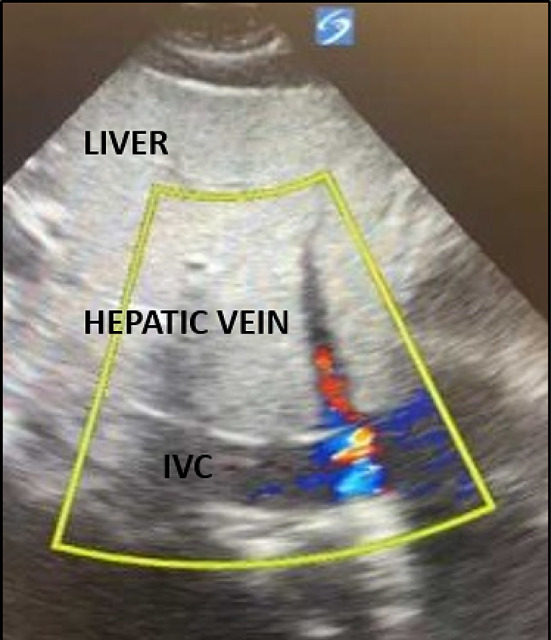

背景:护理点超声(POCUS)已成为重症监护室(ICU)评估危重病人的主要方法。ECMO 患者在重症监护室长期住院期间很容易出现并发症,包括插管错位,从而造成不良后果。尽管有关超声波在 ECMO 患者身上的作用的文献很多,但在插管错位的识别方面,还缺乏放射成像与超声波的直接比较:作者发现了四名通过 POCUS 发现插管错位的患者,而这些患者在常规放射成像检查中被漏诊。插管错位的识别和纠正改变了他们的 ECMO 疗程:本系列病例是首次在文献中证明超声在 ECMO 插管错位方面可能优于放射影像。有必要对此进行进一步研究。

Background: Point-of-care ultrasound (POCUS) has become a mainstay in the evaluation of critically ill patients in the intensive care unit (ICU). ECMO patients are susceptible to complications during prolonged ICU stay, including cannula malposition, which has deleterious consequences. Although the literature surrounding utility of ultrasound on ECMO patients is expansive, direct comparison between radiographic imaging versus ultrasound for identification of cannula malposition is lacking.

Case presentation: The authors identified four patients with cannula malposition discovered through POCUS that was missed on routine radiographic imaging. Identification and correction of malposition changed their ECMO course.

Conclusion: This case series is the first in literature demonstrating that ultrasound may be superior to radiographic images for ECMO cannula malposition. Further investigation into this subject is warranted.